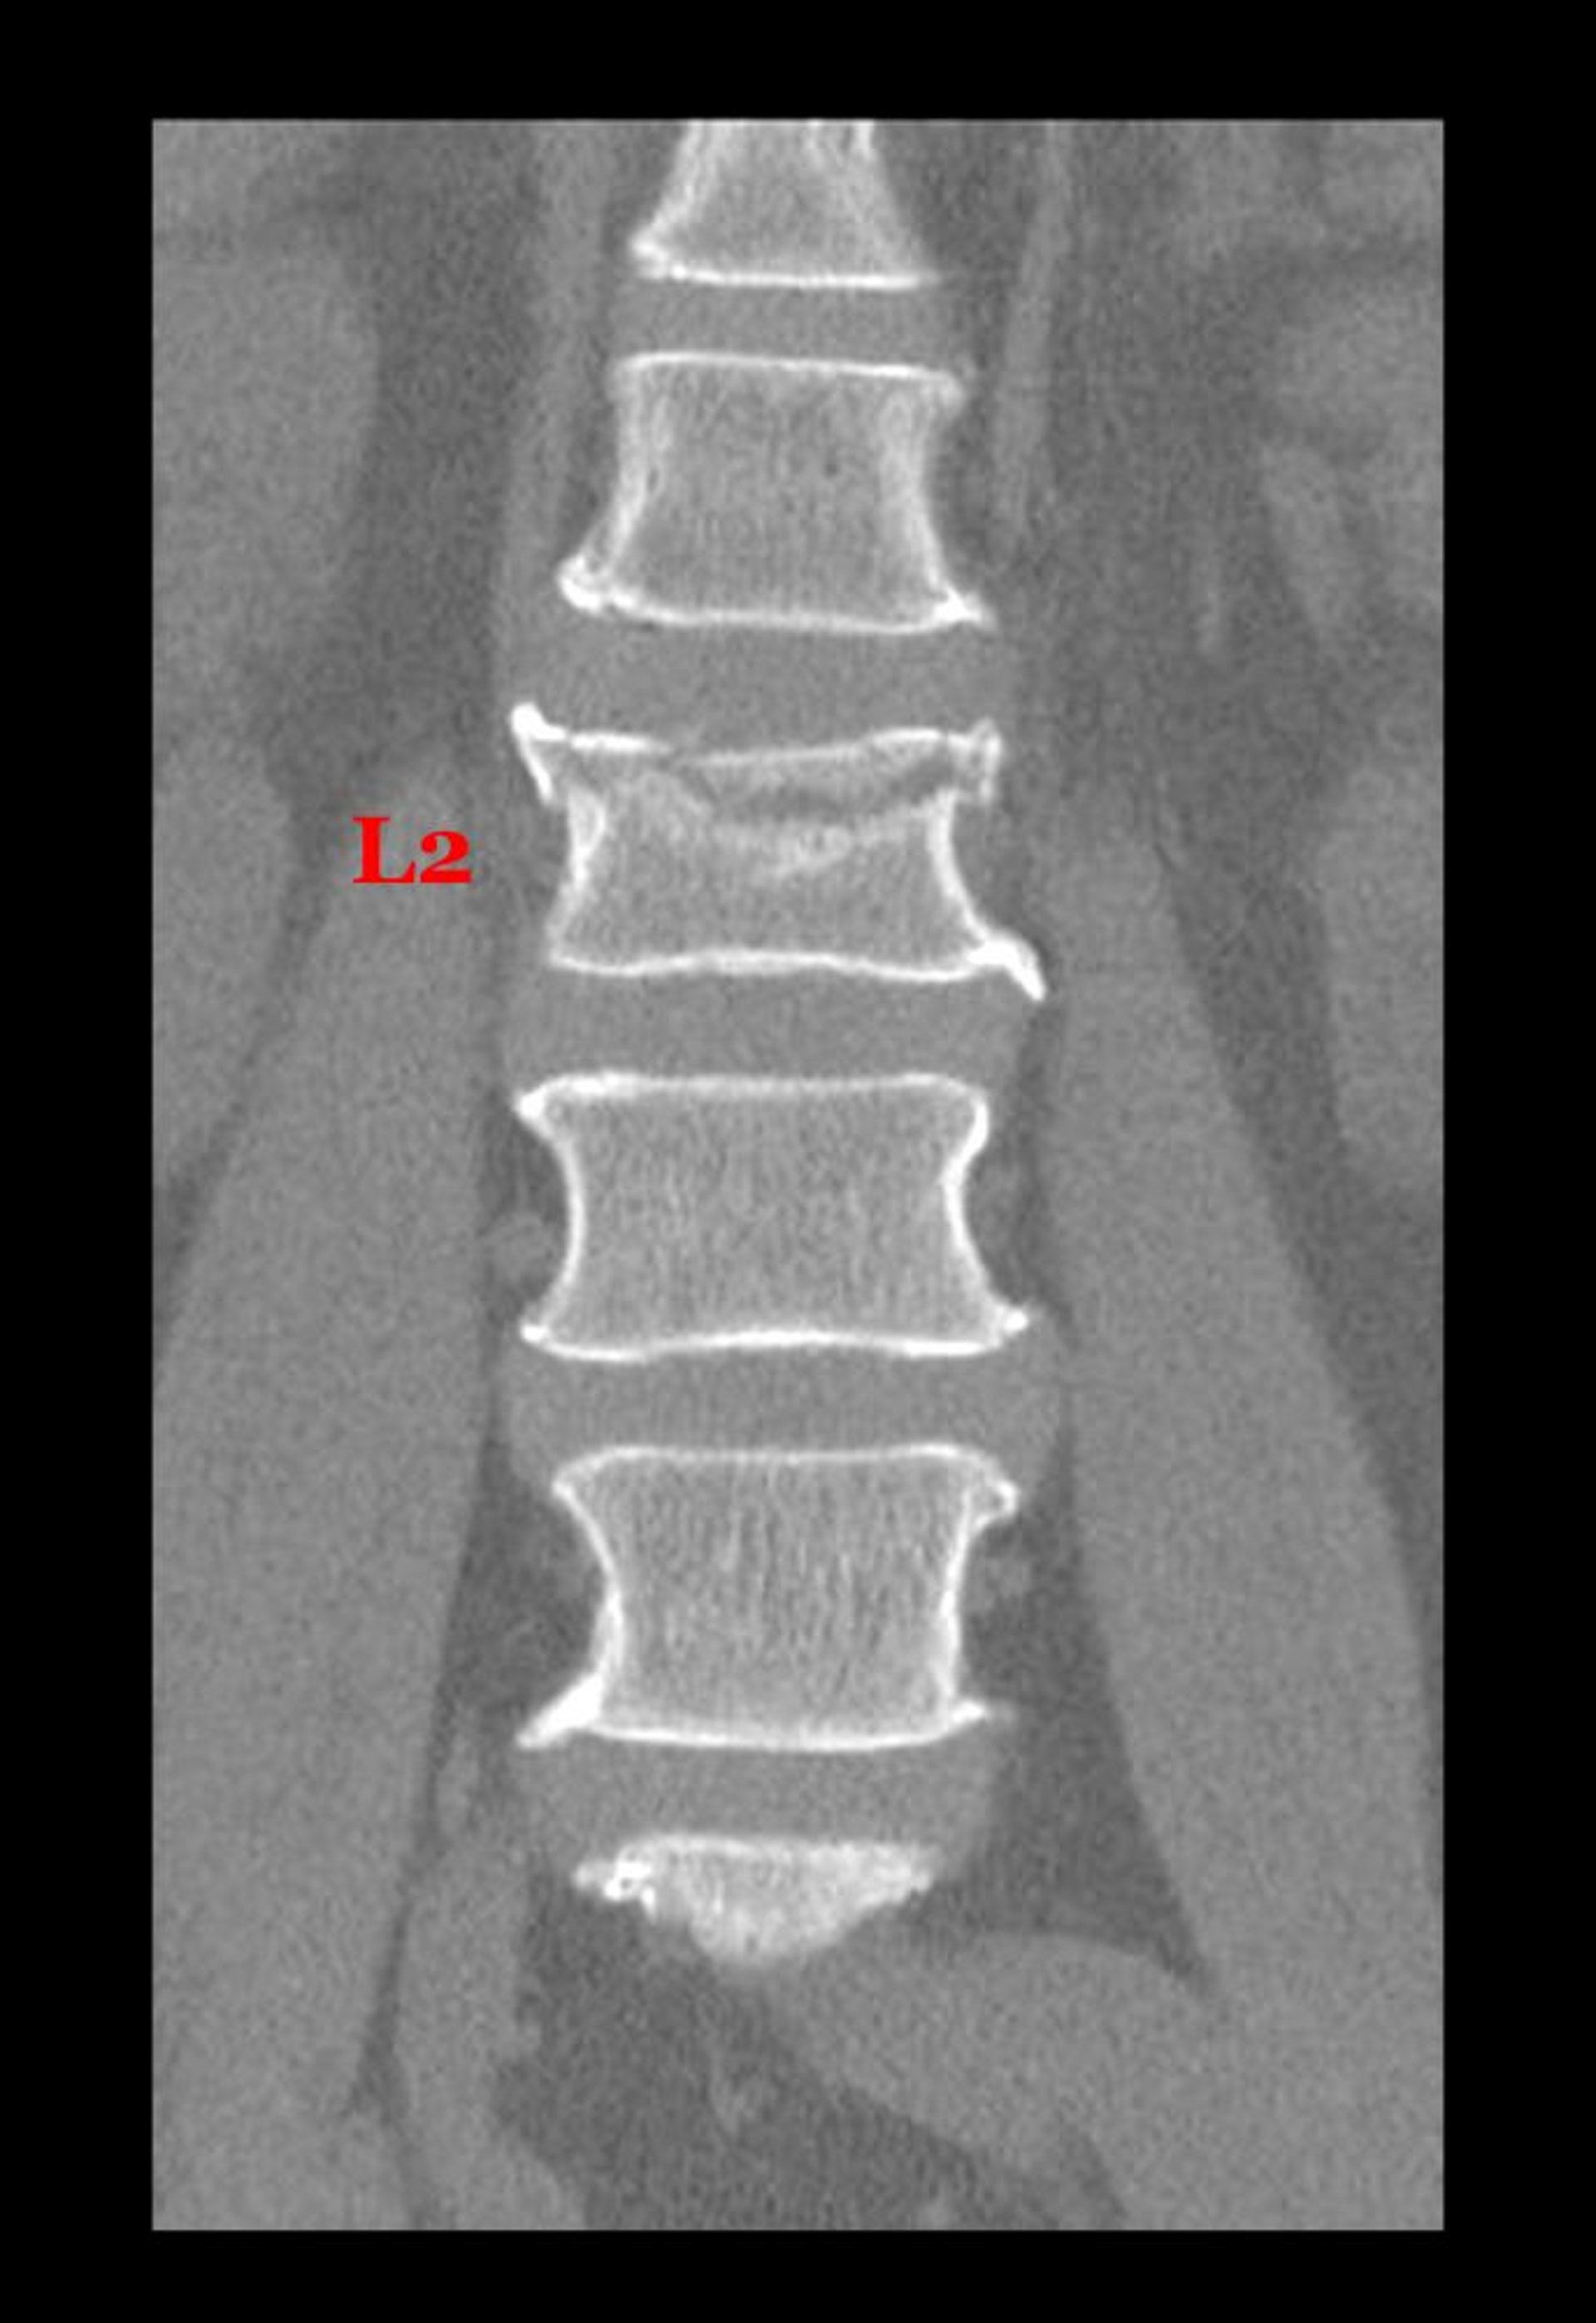

Fractura por compresión de una vértebra lumbar

Esta vista coronal (frontal) procedente de una TC muestra una fractura a través de la parte superior del cuerpo de la segunda vértebra lumbar.